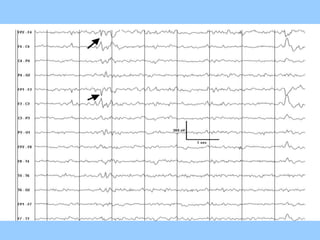

2. Case studies are presented with clinical histories and EEG findings to illustrate different pathologies. Treatment options are also mentioned for many of the conditions.

3. International standards for EEG electrode placement and recording parameters are reviewed. Characteristics of different EEG waves, amplitudes, and patterns are described.